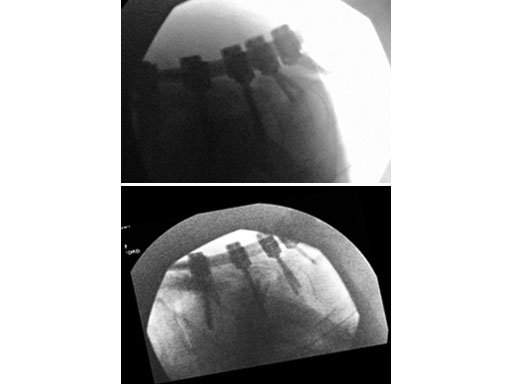

A 28-year-old, 109 kg man was involved in a high-speed motor vehicle collision with C7-T1 jumped facet and T1 teardrop fracture. The patient had ASIA E with motor score of 100. He had failed closed reduction in the emergency room then was taken to OR emergently for open reduction and C5-T2 posterior segmental instrumentation with synapse 4.0. The patient did well postoperatively with no evidence of collapse or failure.

Synapse 4.0 was the ideal solution to treat this injury. This was a heavy patient with a highly unstable injury at the cervicothoracic junction. Synapse 4.0 enabled stabilization of his injury with a rigid construct. It has all the benefits of the 3.5 system but is more rigid and allowed use of one system as opposed to using the 3.5 system and a 6.0 rod system with the nuances of a tapered rod. The author was able to place C5 and C6 lateral mass screws utilizing the Magerl technique and C7, T1, and T2 pedicle screws.